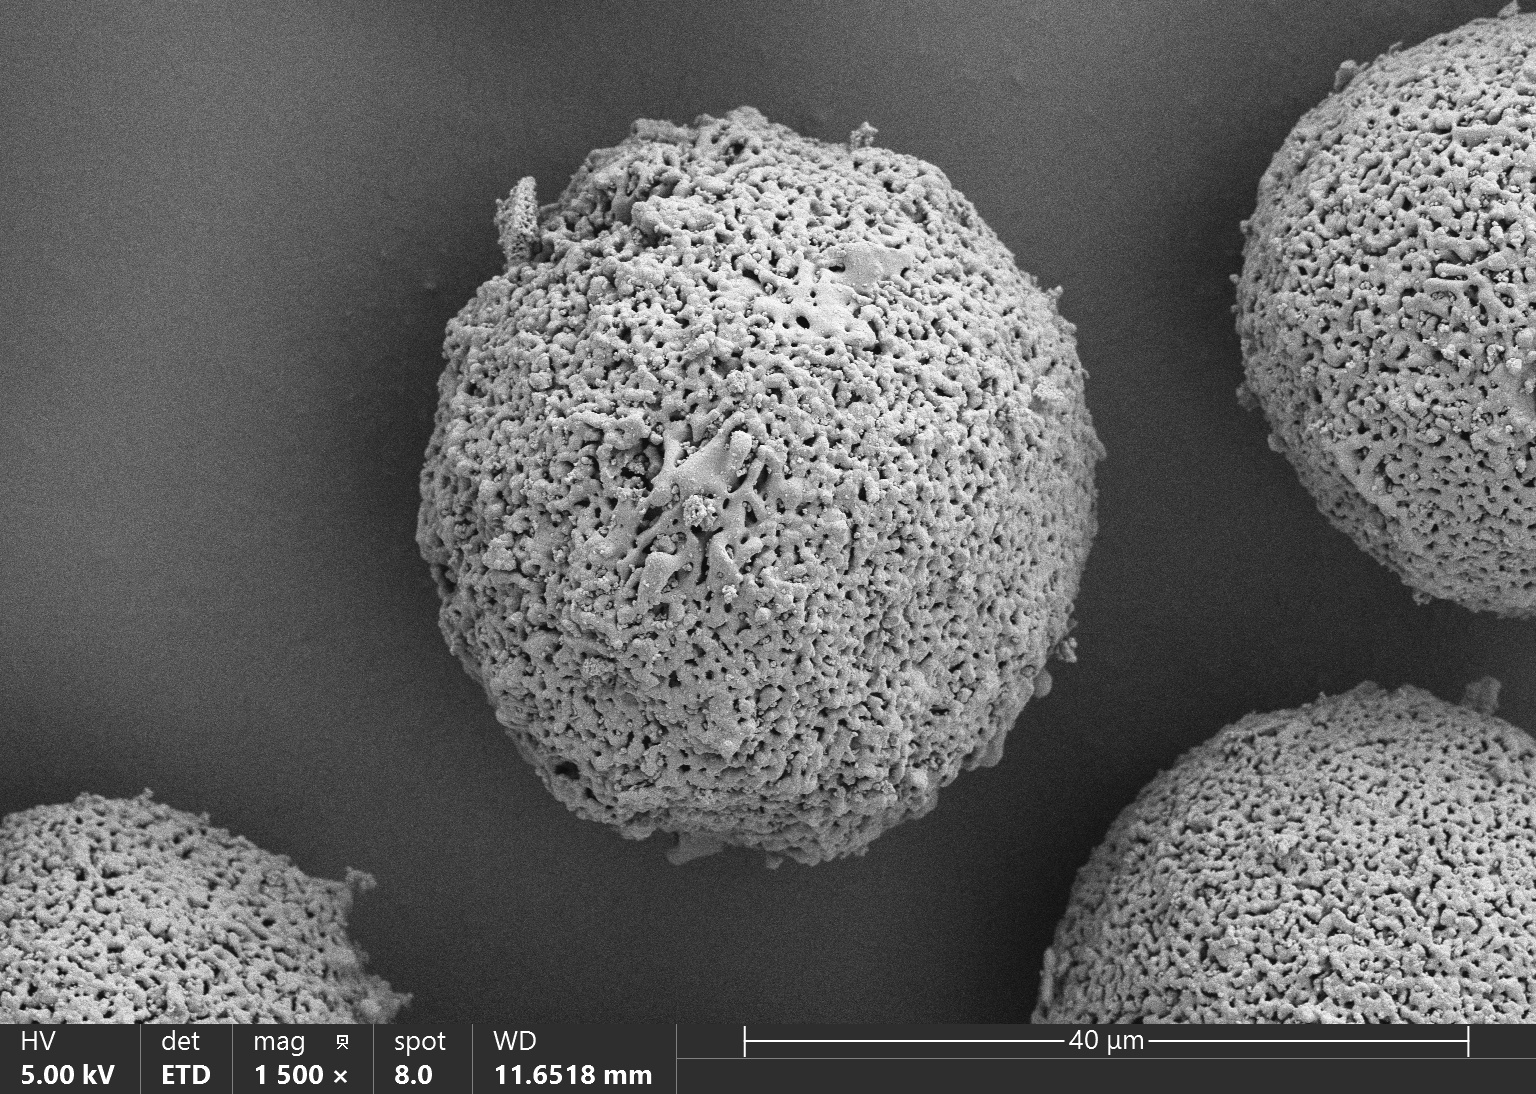

Vita Spire has developed HAp microsphere products for next-generation aesthetic fillers. We offer three different products, each varying in porosity, which corresponds to different degradation rates after injection. Our HAp microspheres provide versatile options for creating specialized, high-quality aesthetic treatments.

| HAPAI-01 | Hydroxyapatite (HAp) Microspheres for Aesthetic Injection, Type I | N/A | Details |

| HAPAI-02 | Hydroxyapatite (HAp) Microspheres for Aesthetic Injection, Type II | N/A | Details |

| HAPAI-03 | Hydroxyapatite (HAp) Microspheres for Aesthetic Injection, Type III | N/A | Details |